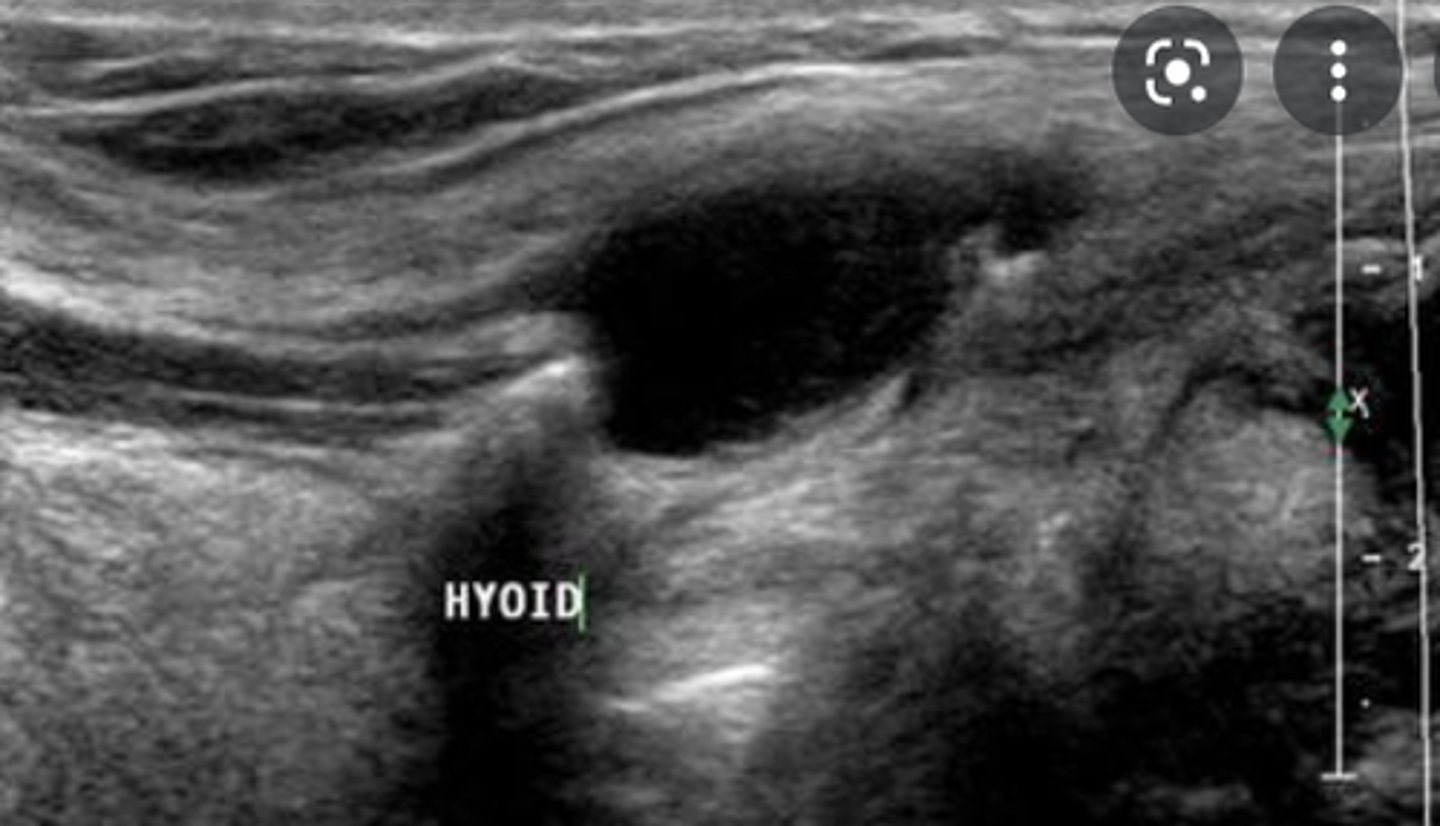

Cysts of the Neck - Thyroglossal cyst:

Etiology

-_____ remnant

Clinical findings

-Asymptomatic

-Palpable _____ _____ neck mass

Sonographic findings

-____echoic superficial neck mass

-Located between the _____ and the _____

-May demonstrate internal _____

-Document relationship to _____ (e.g., inferior)

-Embryonic remnant

-Palpable superficial anterior neck mass

-Anechoic superficial neck mass

-Located between the tongue and the thyroid isthmus

-May demonstrate internal debris

-Document relationship to hyoid bone (e.g., inferior)